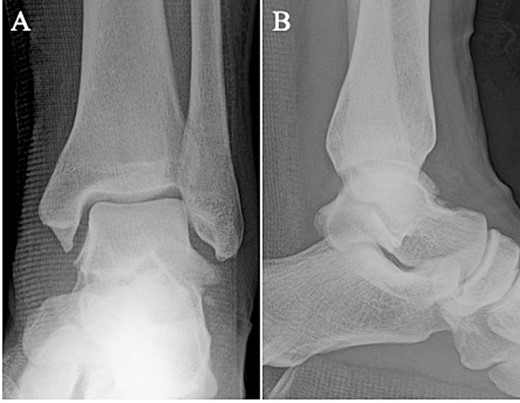

A 24-year-old male basketball player presented to our hospital complaining of left lateral ankle pain during a cutting motion. His height, weight, and body mass index were 172 cm, 64.0 kg, and 21.6 kg/m2, respectively, and he had no history of previous medical conditions. On his first visit to our hospital, he could not walk due to pain. Physical examination revealed swelling, ecchymosis, and tenderness at the lateral aspect of his left ankle. The American Orthopedic Foot and Ankle Society (AOFAS) score was 32 out of 100 points. Plain radiographs of the left ankle showed no abnormal findings in the anteroposterior view, but a fracture line was discovered at the base of the lateral process of the talus in the lateral view (Fig. 1). Non-contrast computed tomography (CT) showed a simple fracture line that extending from the talofibular articular surface down to the posterior talocalcaneal articular surface of the subtalar joint. In addition, the bone fragment was displaced >2 mm (Fig. 2). The patient was diagnosed with Type I LPFT and underwent surgical treatment.

Non-contrast CT showed a simple fracture line that extending from the talofibular articular surface down to the posterior talocalcaneal articular surface of the subtalar joint in the coronal (A) and sagittal (B) views.